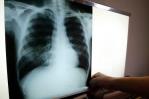

El Hospital Doctor Francisco Moscoso Puello informó que en lo que va del año 2022, la Unidad de Tuberculosis del centro ha atendido a 287 pacientes de tuberculosis, por lo que instó a la población a prestarle atención a los síntomas de esa afección, específicamente la tos frecuente.

El hospital Moscoso Puello informó que cuenta con una unidad especializada y con los servicios de consultas, acompañamiento, diagnóstico, tratamiento, conserjería, pruebas como Gene-xpert, Cultivo de esputo (Prueba de Sensibilidad) y Baciloscopia (BK).